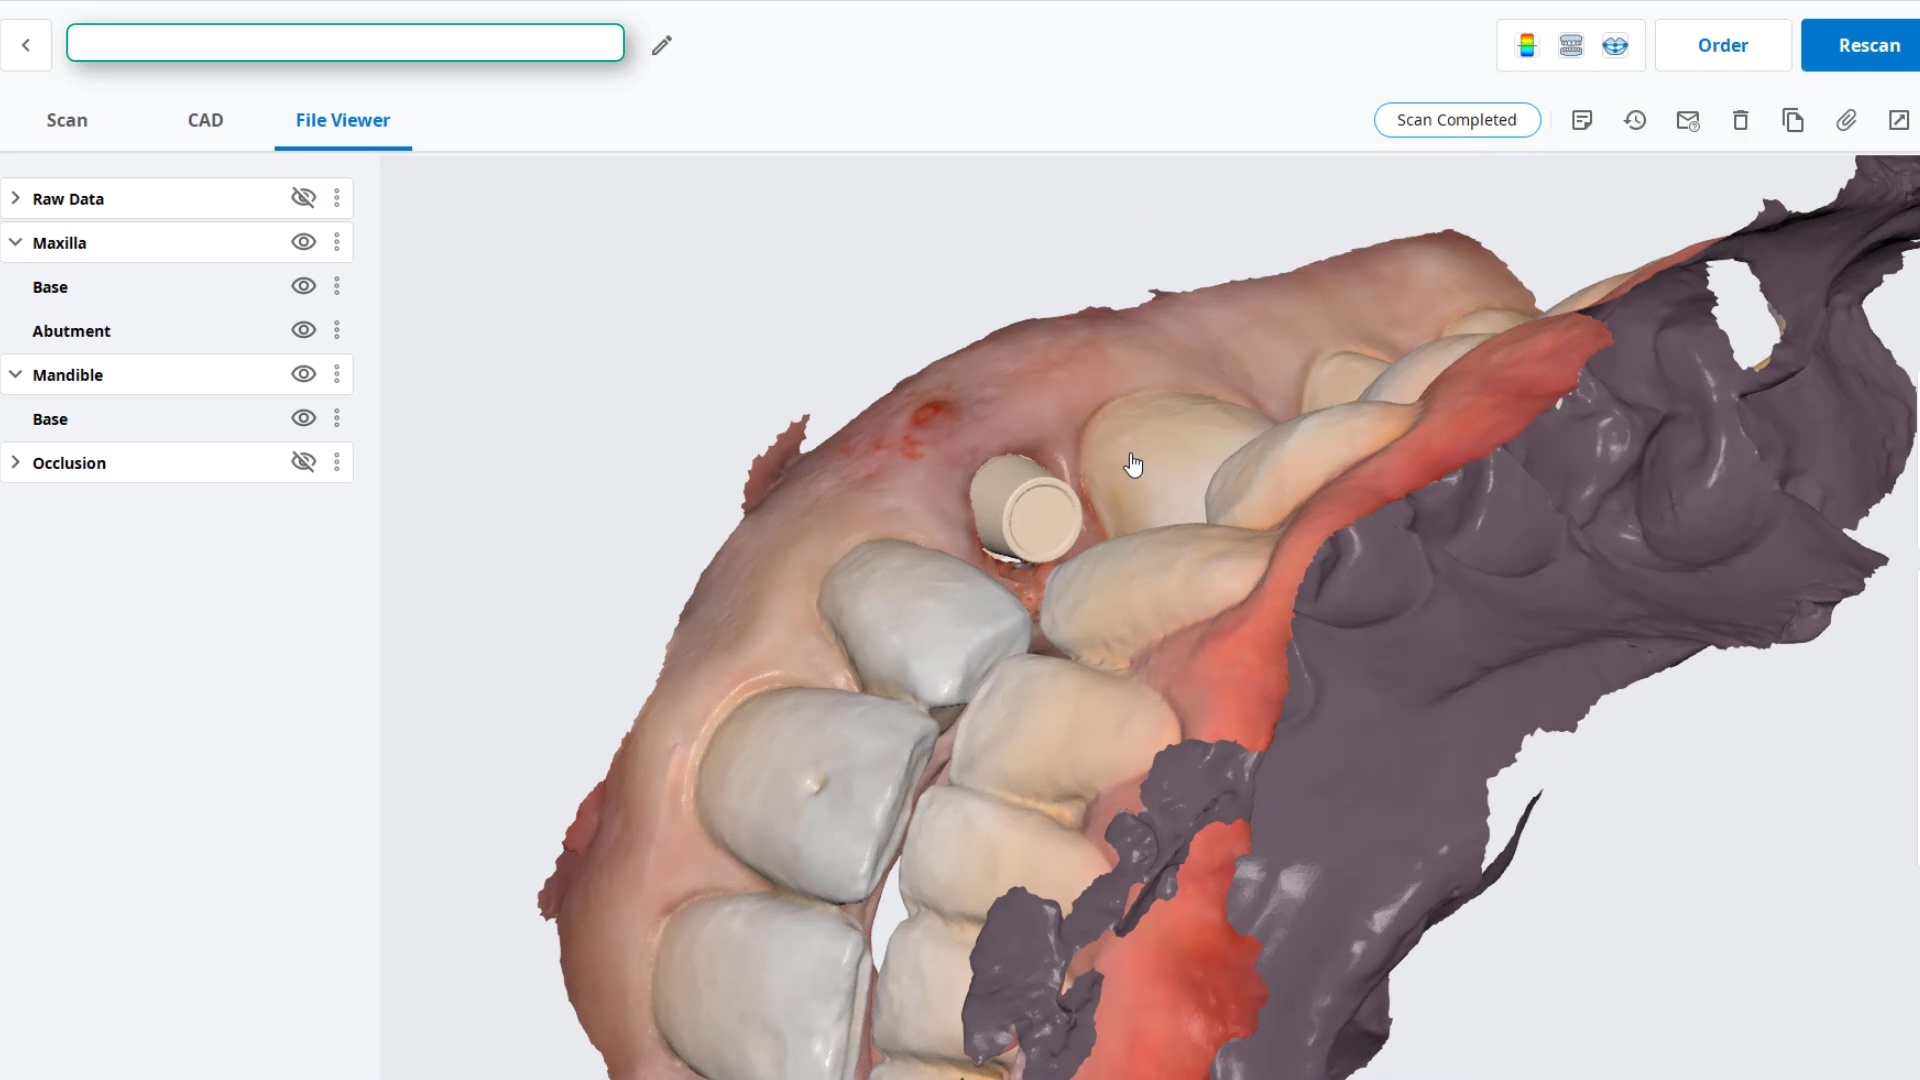

Using the CT as a Remount Jig If You Have Lost The Vertical Dimension For Some Reason or Another

November 20, 2020At CAD-Ray, we have now designed over 20,000 implant cases since 2013. One of the most common requests we get is from doctors doing full arches and their desires to […]